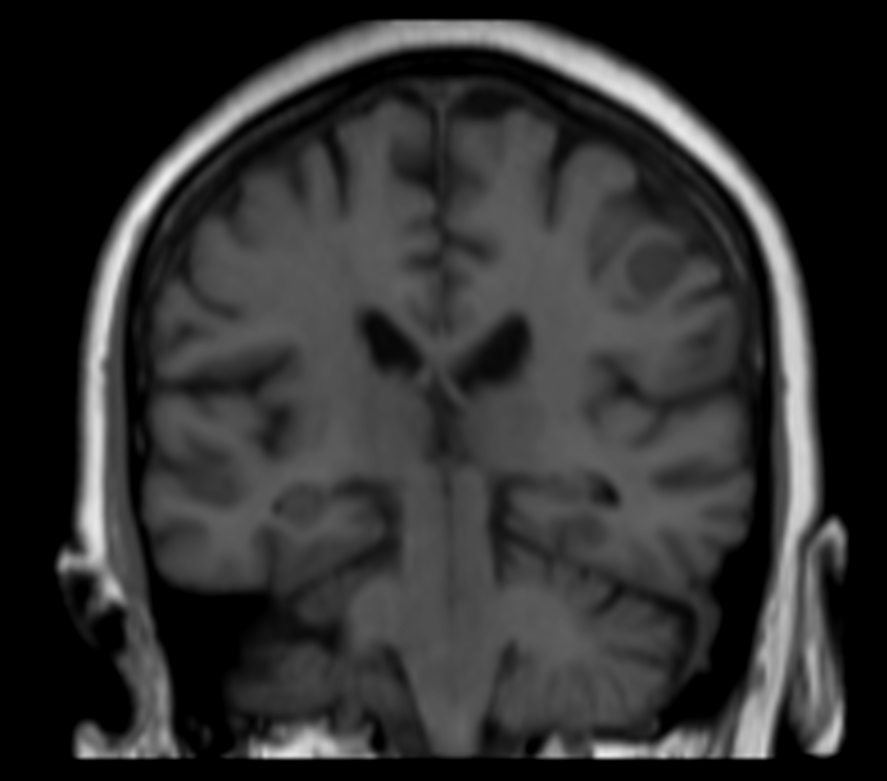

Female with one metastasis of pulmonary cancer underwent MRI simulation in the radiotherapy positioning mask on Ingenia MR-RT 1.5T before stereotactic radiation therapy with 25 Gy in 3 fractions.

3D T1w FFE (coronal reformat) pre contrast